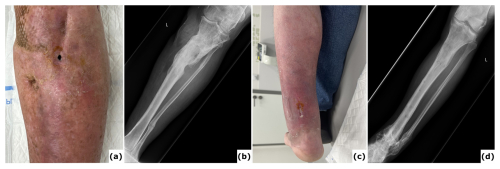

Figure 1A case of polymicrobial fracture-related infection (FRI) of the femur resulting from a gunshot injury is described. A 44-year-old polytrauma patient presented with multiple injuries, including a Gustilo-Anderson type III open femur fracture of the left lower limb. (a) The patient was transferred after initial stabilization, external fixation of the left femur, and several surgical wound debridements. (b) Anteroposterior radiograph of the left femur was taken following acute shortening, distal corticotomy, and lengthening. No cultures were collected during this surgery. (c–d) Computed tomography (CT) images of the left femur at 6 months show a persistent unhealed fracture site along with a distal distraction site that is not fully consolidated. Due to the presence of suggestive signs of FRI (local redness, swelling, and elevated serum inflammatory markers), local debridement of the fracture site was undertaken. Cultures grew Klebsiella pneumoniae and Enterococcus faecalis, for which the patient received systemic antibiotic therapy (6 weeks). (e) Clinical image of a classic ring fixator. (f–g) Lateral and anteroposterior radiographs after removal of the external fixator at 2 years demonstrate consolidation of the fracture and the distal distraction site. Because of continued pin site infections, local redness, and elevated serum inflammatory markers, the intramedullary canal was reamed and cultures were obtained, all of which were positive for Staphylococcus aureus. Again, the patient received systemic antibiotic therapy (6 weeks). (h) Clinical images of the lower limb 1 year after removal of the external fixator show significant scarring of the left thigh from the pin tracts. Knee flexion was limited to 10°. This case shows that long-term external fixation is not harmless and can be associated with several potential complications, such as joint contracture, scarring from the pin tracts, and severe chronic infections.